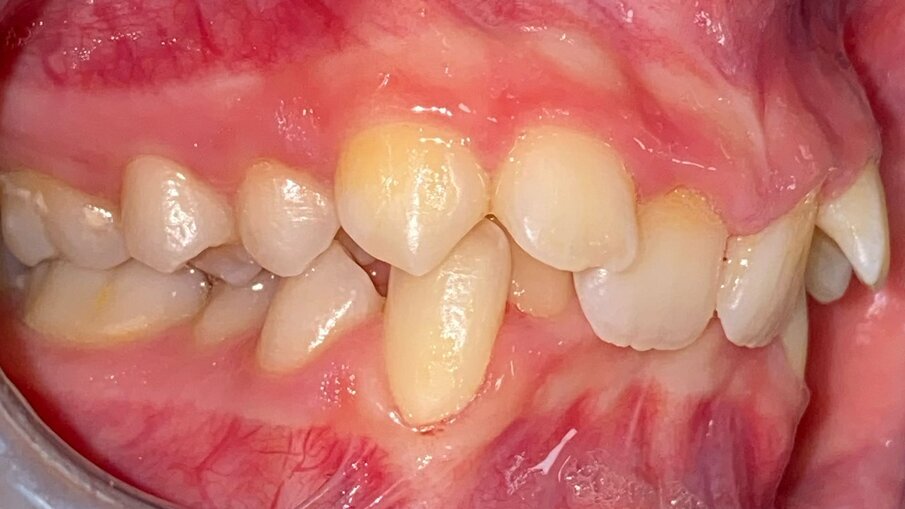

All’esame obiettivo intraorale si riscontra sul piano frontale un severo morso profondo con precontatto traumatico degli incisivi superiori contro la papilla retroincisiva e le rughe palatine anteriori durante la massima intercuspidazione, con overbite di 10 mm (Fig. 5). Dalle foto laterali si evidenzia una malocclusione di Classe II divisione 2 con scissor bite dell’elemento 1.5 (Figg. 6, 7), mentre dalle foto occlusali si rileva un grave affollamento con contrazione di entrambe le arcate maggiore nella zona premolare (Figg. 8, 9). L’analisi di Bolton mostra un eccesso superiore 3-3 di 2,34 mm (73,6%) e 6-6 di 2,76 mm (88,8%). L’analisi cefalometrica evidenzia una Classe II scheletrica, modello facciale normodivergente, angolo interincisale aumentato, incisivi superiori e inferiori retroinclinati (Fig. 10). La radiografia panoramica mostra la presenza dei germi dei terzi molari, assenza di parallelismo tra le radici dei premolari inferiori (Fig. 11) e una sovraeruzione degli incisivi inferiori che crea un doppio piano tra gli incisivi e i molari, segno di una curva di Spee molto profonda.

Fig. 7_Laterale sinistra pre-trattamento.